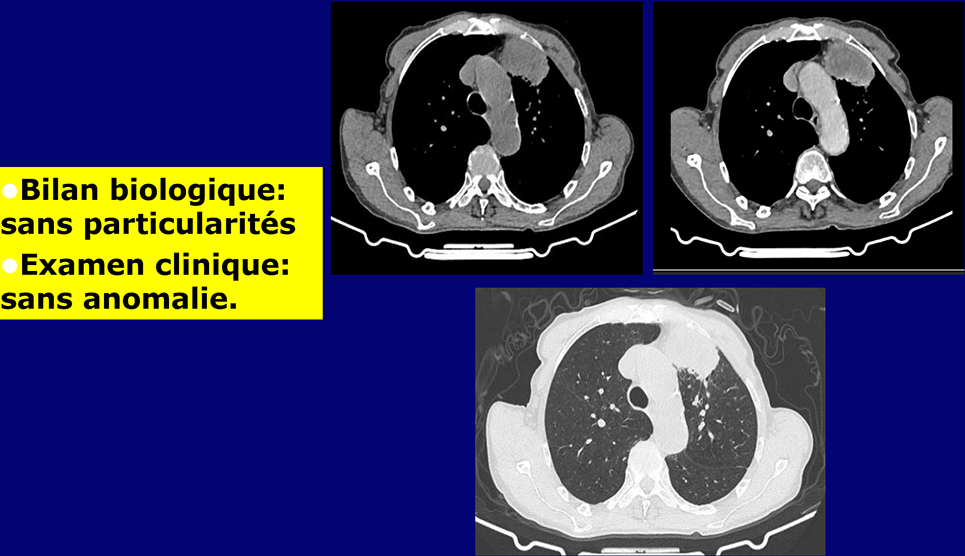

Homme de 79 ans, Ancien tabagique, sevré il y a 18 ans.

Présente depuis 6 mois une hémoptysie intermittente

Sans autres signes respiratoires dans un contexte d'apyrexie et d'asthénie

2 / 5

3 / 5